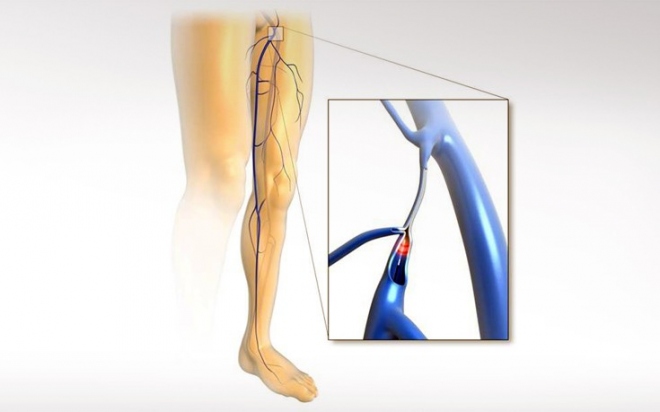

Η εμφάνιση κιρσών είναι συνήθως αποτέλεσμα της φλεβικής ανεπάρκειας του επιφανειακού φλεβικού δικτύου που συναντάται στο 40% των γυναικών και στο 20% των ανδρών. Η ανεπάρκεια των φλεβικών βαλβίδων επιτρέπει την παλίνδρομη ροή αίματος και δημιουργεί συσσώρευση αίματος που λιμνάζει στις φλέβες οι οποίες διαστέλλονται, επιμηκύνονται και αποκτούν σχοινοειδή μορφή με πιθανές ελικώσεις. Οι παθολογικές αυτές φλέβες ονομάζονται κιρσοί.

Από το 2000, μια σειρά από ελάχιστα επεμβατικές ενδοφλεβικές τεχνολογίες (laser, rf, σκληροθεραπεία) άλλαξαν σημαντικά τον τρόπο αντιμετώπισης των φλεβικών παθήσεων.

Οι σύγχρονες επιστημονικές οδηγίες σε Ευρώπη, Αμερική, Ιαπωνία, κ.α. προτείνουν πλέον ως βασική επιλογή για τη θεραπεία των κιρσών των κάτω άκρων τις ενδοφλεβικές μεθόδους (laser, rf) ενώ η σαφηνεκτομή περιορίζεται μόνο σε περιπτώσεις που δεν μπορούν να εφαρμοστούν οι σύγχρονες τεχνικές. Η θεραπεία των κιρσών με ενδοφλεβικό laser αποτελεί παγκοσμίως την πλέον δημοφιλή και αποτελεσματική θεραπεία. Σήμερα στις ΗΠΑ περίπου τα 3/4 των επεμβάσεων πραγματοποιούνται με τη χρήση ενδοφλεβικού laser.

Ανώδυνη ενδοφλεβική θεραπεία των κιρσών με δακτυλίους laser

Τα σημαντικά πλεονεκτήματα των ενδοφλεβικών θεραπειών οδήγησαν στην ανάπτυξη αρκετών εναλλακτικών επιλογών (laser διαφόρων ειδών, ραδιοσυχνοτήτων, μηχανικών, χημικών σκευασμάτων, κ.τ.λ). Σήμερα, μια νέα γενιά ανώδυνων laser με ειδικούς ενδοφλεβικούς καθετήρες καθιστά την θεραπεία των κιρσών ακόμη πιο ανώδυνη, ασφαλή και σίγουρη έναντι κάθε άλλης διαθέσιμης τεχνικής όπως επίσης και έναντι των laser της προηγούμενης γενιάς.

Η νέα γενιά ανώδυνων laser με ειδικούς ενδοφλεβικούς καθετήρες διπλών δακτυλίων εκπομπής (laser double-ring 360ο) επιτυγχάνει την θεραπεία των κιρσών με τη εφαρμογή ελάχιστης, αλλά απόλυτα εστιασμένης, ενέργειας στα τοιχώματα του αγγείου. Η εστιασμένη δράση του laser συρρικνώνει ομοιόμορφα τα τοιχώματα και σφραγίζει οριστικά και με απόλυτη ασφάλεια την πάσχουσα φλέβα ελαχιστοποιώντας το ενδεχόμενο επιπλοκών (αιματωμάτων, μετεγχειρητικού πόνου, κ.α.).

Η θεραπεία μπορεί να πραγματοποιηθεί χωρίς νάρκωση και νοσηλεία, συχνά δεν απαιτεί καθόλου τομές και δεν αφήνει ουλές. Η κινητοποίηση του ασθενούς είναι άμεση και τα ποσοστά υποτροπών μικρότερα του 5%. Αποτελεί ιδανική επιλογή θεραπείας της μείζονος και της ελάσσονος σαφηνούς, ακόμη και σε ασθενείς με συνοδά προβλήματα (σε αντιπηκτική αγωγή, παχύσαρκους, διαβητικούς, κ.α.). Σήμερα, με την χρήση των πιο εξελιγμένων τεχνολογιών μπορούμε να προσφέρουμε στους ασθενείς αμεσότερη και ακριβέστερη διάγνωση, ανώδυνη και αποτελεσματική θεραπεία, απαλλάσσοντας από τα βασανιστικά συμπτώματα των φλεβικών παθήσεων.